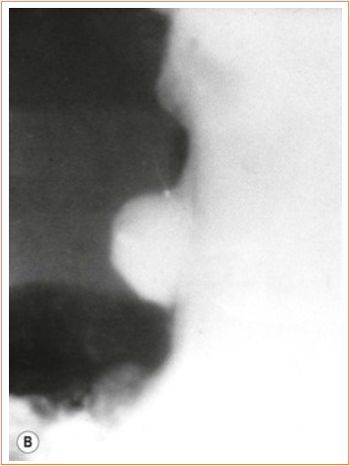

Features suggesting a malignant gastric ulcer

NOTE: Remember Hampton’s (Harmless = benign) and Carman (Carcinoma = malignant)

malignant ulcer with a carmen meniscus sign